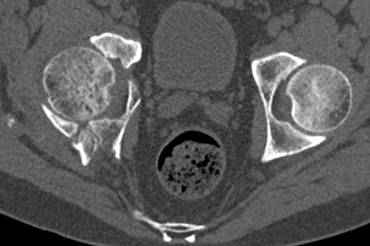

высылаю дополнительно сканы.

итак, второй вариант: высокий двухколонный с вовлечением КПС... Ни одно из основных повреждений не репонировано, кроме задней стенки. Скорее всего попытка реконструкции вертлуги сейчас будет очень травматичной и не очень эфективной, т.е. вероятный риск более значим, чем ожидаемая польза... Лучше подождать, и потом сразу эндопротез